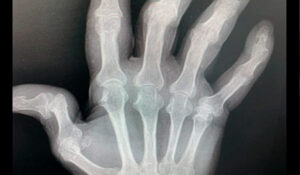

Cirugía de Primer Nivel en Mano y Extremidad Superior para Pacientes de República Dominicana

El Dr. Alejandro Badia ofrece a los pacientes de República Dominicana un acceso facilitado a Miami para atención especializada de clase mundial en condiciones de mano, muñeca y codo.